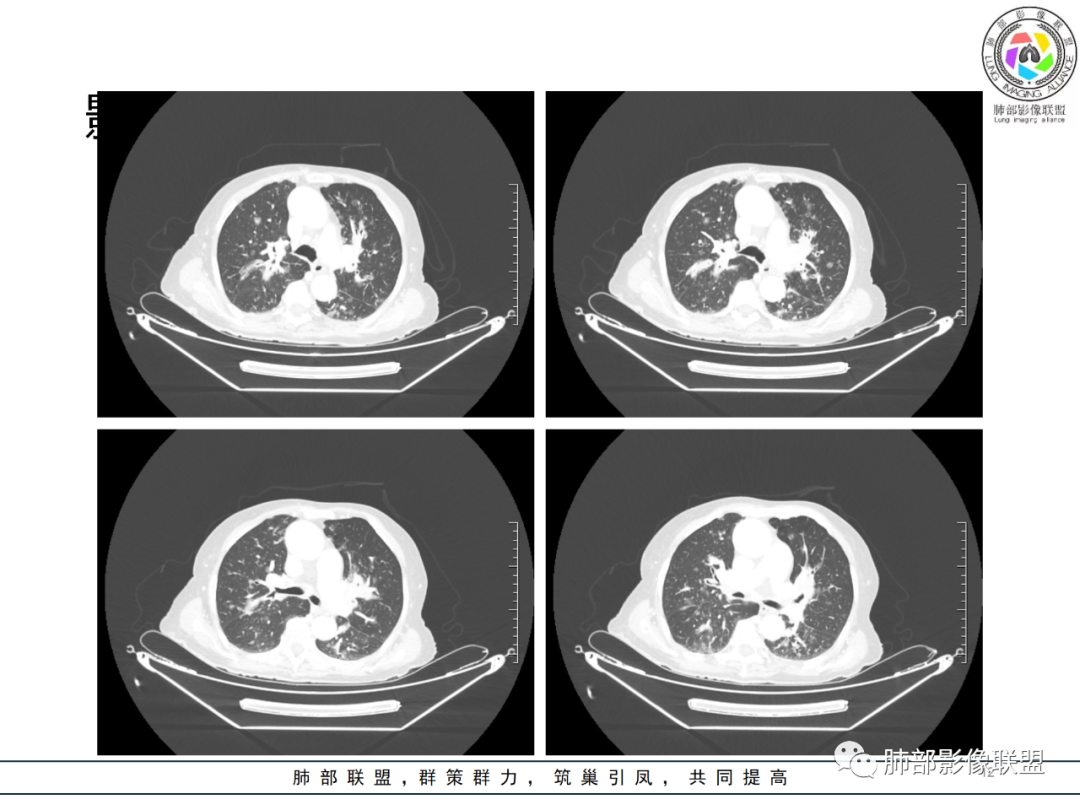

影像资料

82岁女性,反复发热入院,查外周血白细胞升高,抗生素治疗可缓解,支持细菌感染性发热,结合肾脏肿瘤,考虑泌尿系感染发热;CT提示双肺多发毛玻璃影,右下肺多发大结节影,3月复查,双上肺毛玻璃影/混合毛玻璃影增多,部分呈点晕征,右下肺多发肿块,可见支气管穿行,双下肺中轴间质增厚,左肾占位,肺部病变考虑:1.淋巴瘤 2.肾癌肺转移

右肺下叶近胸膜面多个实性结节,复查体积明显增大,多个新增实性及混合磨玻璃结节,边缘晕征,左肾及肾上腺占位,考虑囊性肾癌肺内、肾上腺转移。

右肾肾上腺,左肾及肾周软组织,脾脏可疑病变,双肺结节斑片支气管血管束叶间裂分布。一元考虑大B淋巴瘤多器官浸润。鉴别小细胞,尿路上皮癌转移,igg4

老年女性,近期反复的发热,胸部CT基础尚可,心影增大,双肺下叶血管束增粗,3个月后复查 提示双肺多发磨玻璃密度影,并有磨玻璃影内部血管的穿行,双肺下叶血管束的增粗,纵隔窗下未见纵隔肿大的淋巴结,血管通畅,未见血管壁的增厚,左肾肿瘤?肺内病变不符合支气管束分布,暂不考虑吸入性,考虑淋巴管或血管源性病变。总体考虑非感染性病变可能性大,血管炎?淋巴瘤?

升结肠应该也有问题,腹膜后也是多发的肿大淋巴结,肾上腺也受累,中轴间质的增厚,我始终觉得是增生性病变,支气管也没有扩张,它有占位效应,还有些磨玻璃边界偏清,这个中轴间质伴增生性病变这是个关键。

结果:弥漫大B淋巴瘤

如果说两肺病变生就一张“大众脸”,但腹部异常影像却带给我们一些重要线索! 双肾病变变现为浸润性累及肾周、延及深静脉,而非典型膨胀性,低密度少血供,腹膜后肿大的淋巴结同样强化不明显,这些都符合典型的浸润性肾淋巴瘤的影像表现。注意患者肾上腺低密度结节影及脾脏多发结节影,脾脏恶性肿瘤尤以淋巴瘤最为常见!